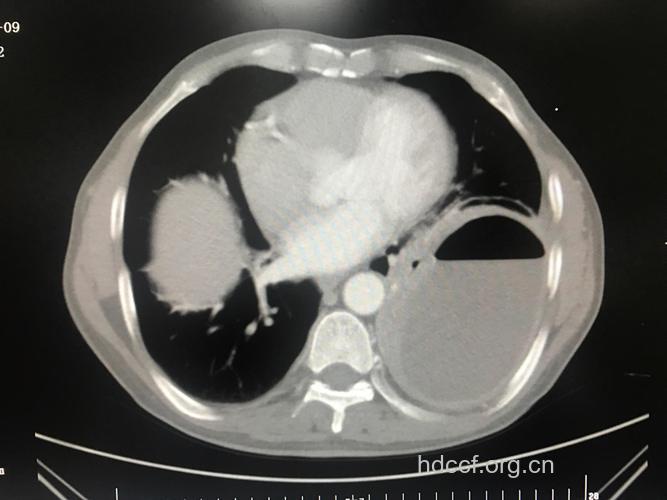

[影像学表现]

1.主要呈空洞病变,多有液平。内外壁界限清楚,并有较长的纤维索条通向四周。

2.同时有肺部慢性炎症、新的播散病灶、肺部纤维化或团块状致密阴影。

3.并发脓胸、脓气胸。